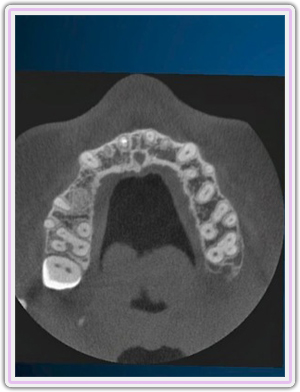

Guided Surgery Planning

CT Scan Imaging

Computer Guided Implant Planning